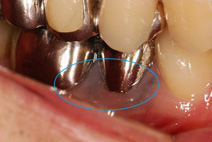

右の写真をご覧ください。

歯を歯茎近くまで削らなくてはならないほど進行した虫歯の写真です。通常なら抜歯後にインプラントや入れ歯で治療することになります。

エクストリュージョン法を用いれば、このような状態でも治療できます。

残った歯を歯茎の上まで引っ張り上げ、被せ物の土台にすることで抜歯を回避するのです。